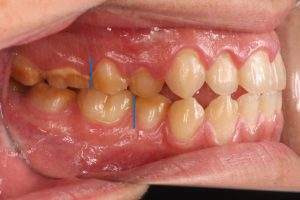

青線で示したように治療前後で上下顎の正中線が改善しています。また、下顎右側臼歯部が後方移動したため右側臼歯の咬合も改善しています。ただし、矯正単独で治療した場合は顎のゆがみは改善しませんので、顔貌の改善を期待する場合は外科矯正が必要です。